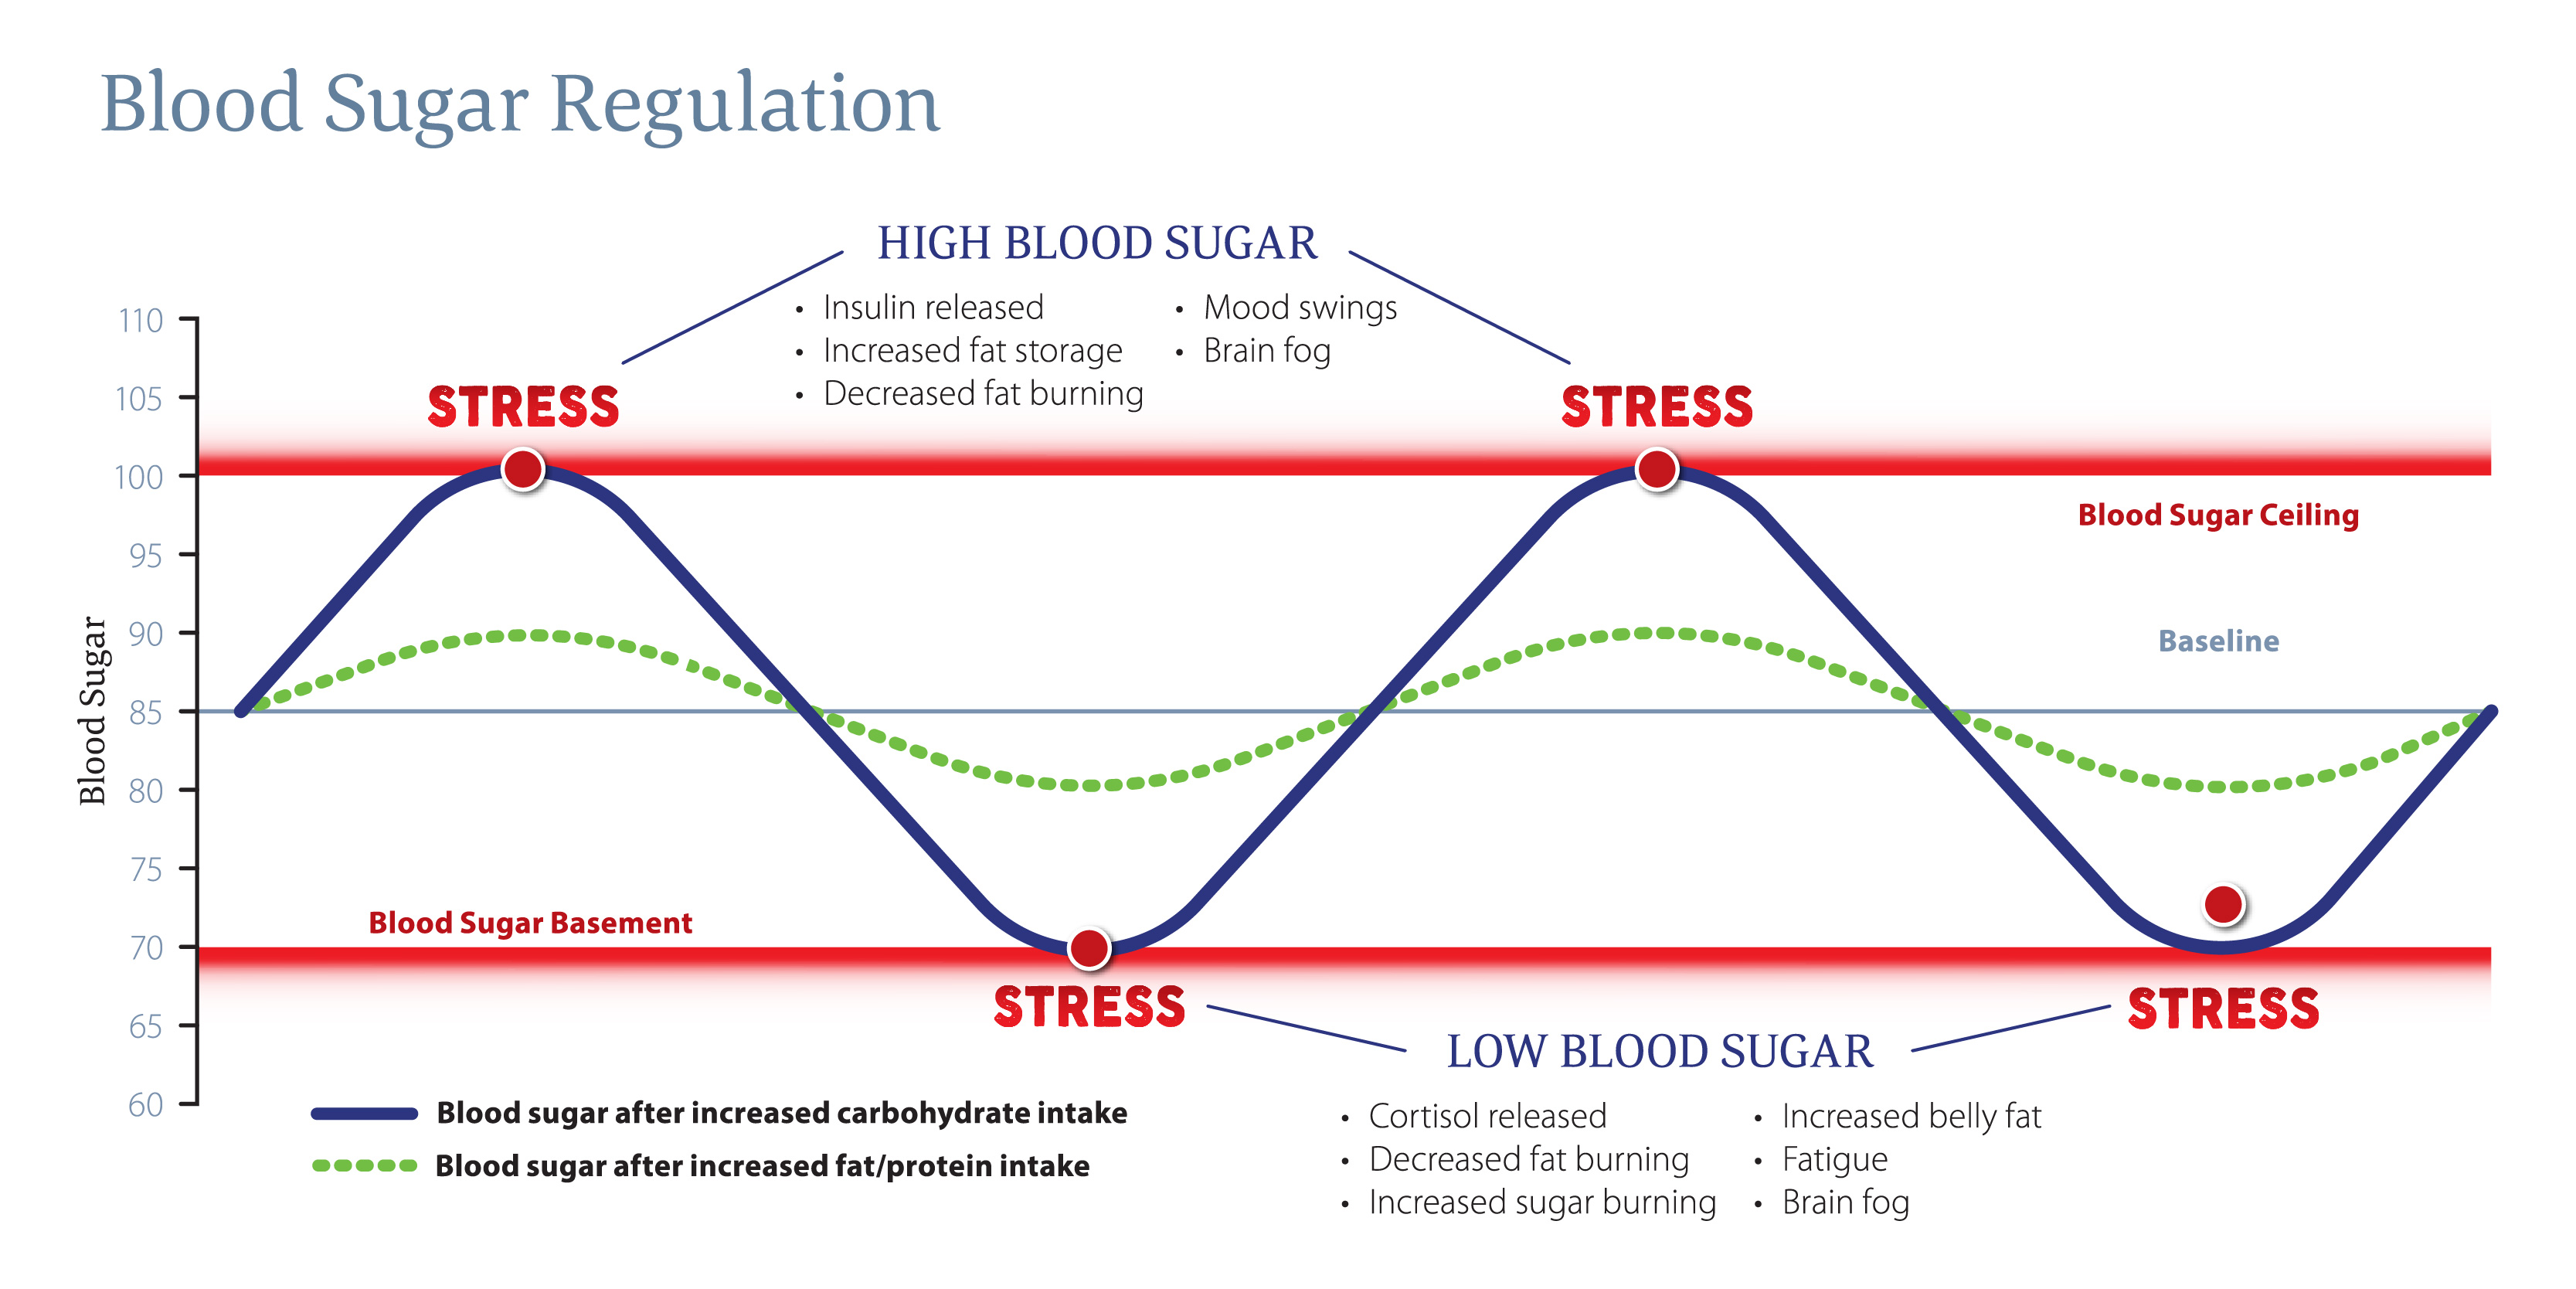

maybe even a fasting blood insulin. If your patients reveal they are eating high glycemic meals or skipping meals regularly, then we can anticipate their blood glucose will spike and crash outside the normal range of 70 to 100 mg/dL.

As we discussed earlier, our body recognizes blood sugar out of a normal range as a stressful event. The response to high blood sugar is to release insulin, the hormone that promotes the absorption of glucose from the blood so it can be used as energy

by the body.4 This happens naturally when we eat a meal. High blood sugar stimulates fat storage, decreases fat burning and can cause mood swings and brain fog. If for whatever reason we go out of that range too often, the body may start

to overshoot insulin release and instead of lowering blood sugar appropriately, we may end up with blood sugar at the basement level, which as you know, is recognized as a stressor to the body. Low blood sugar triggers release of cortisol, which is

widely known as the stress hormone that provides the body with glucose by tapping into stores of glycogen through a process called gluconeogenesis.

Low blood sugar can be the end result of consuming high sugar meals regularly and creating an overcompensating response. It can also be due to skipping meals and not providing the body enough sugar to keep the body energized for daily activity. The symptoms of low blood sugar greatly overlap those of high blood sugar; decreased fat burning, increased belly fat, fatigue and brain fog. They can also be misconstrued as other hormone imbalances such as cortisol, thyroid and sex hormones and even neurotransmitter levels.